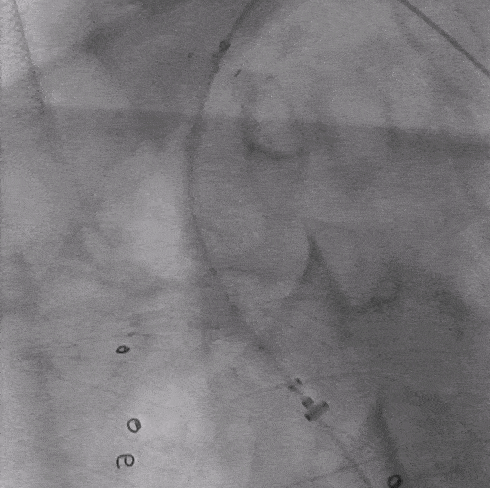

02. 沿左肱动脉穿刺并引入标记导管于升主动脉造影,见左椎动脉优势明显,LSA与LCCA距离小于10mm。

03. 控制性降压至90/55mmHg左右,沿右股动脉入路引入超硬导丝及华脉泰科胸主支架PTBS3430180,术中沿LCCA后缘处缓慢释放1-2节,再次造影确认定位精准后继续释放主体支架,造影示覆膜支架未覆盖LCCA,覆盖LSA。